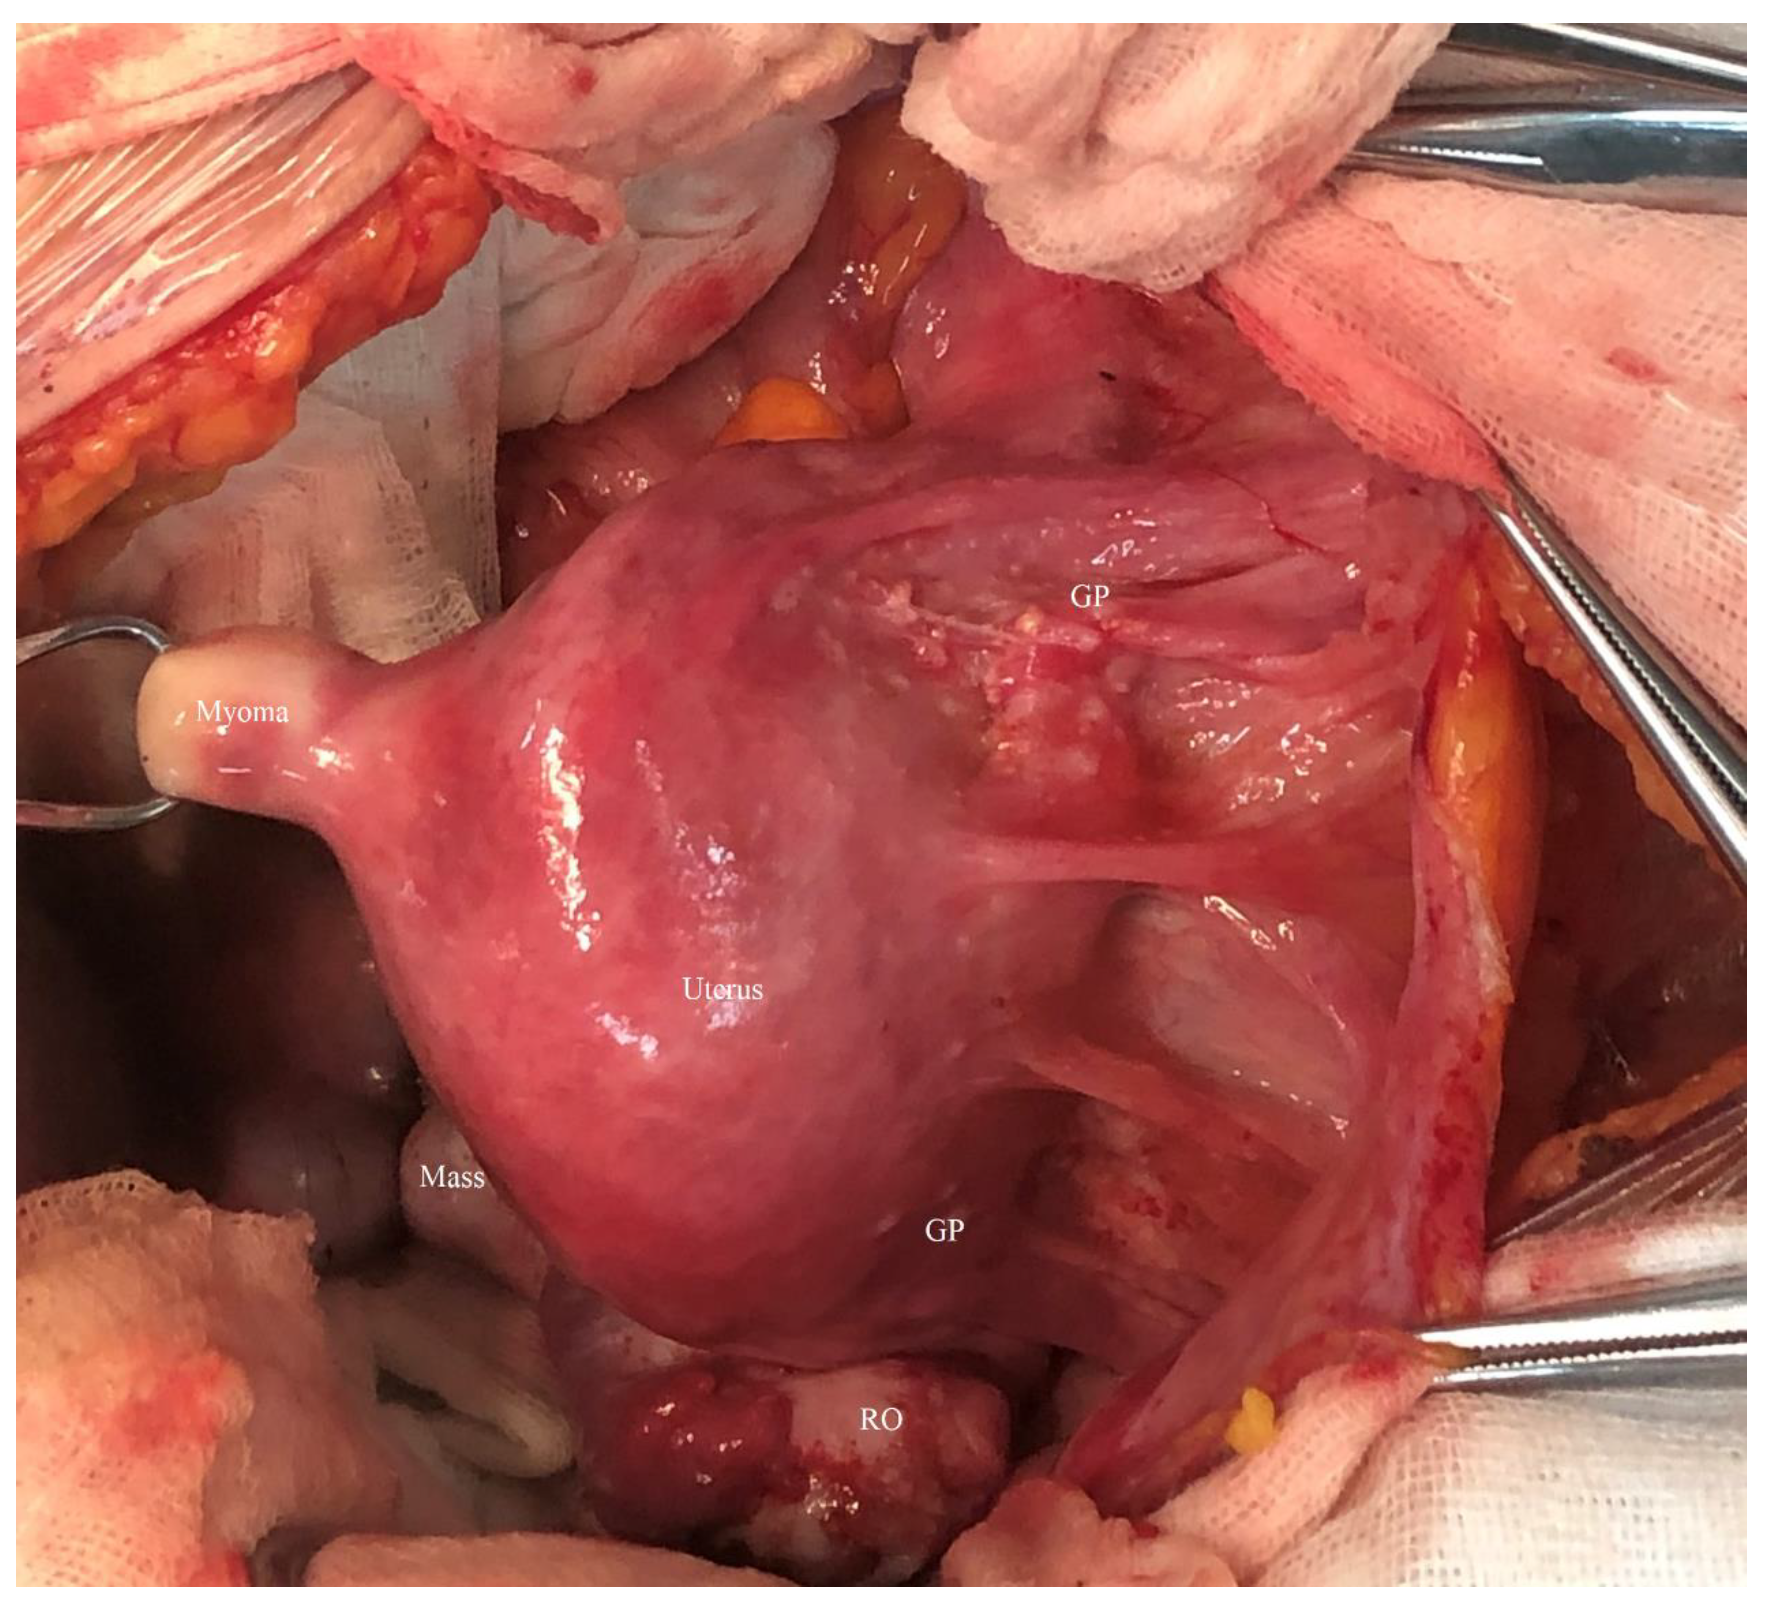

2. Case